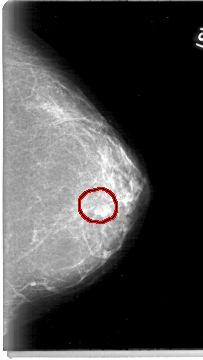

FILE: D_4004_1.LEFT_MLO.OVERLAY

TOTAL_ABNORMALITIES 1

ABNORMALITY 1

LESION_TYPE MASS SHAPE OVAL MARGINS OBSCURED

ASSESSMENT 0

SUBTLETY 3

PATHOLOGY BENIGN

TOTAL_OUTLINES 1

BOUNDARY

LEFT_MLO LINES 5386 PIXELS_PER_LINE 2956 BITS_PER_PIXEL 12 RESOLUTION 43.5 OVERLAY